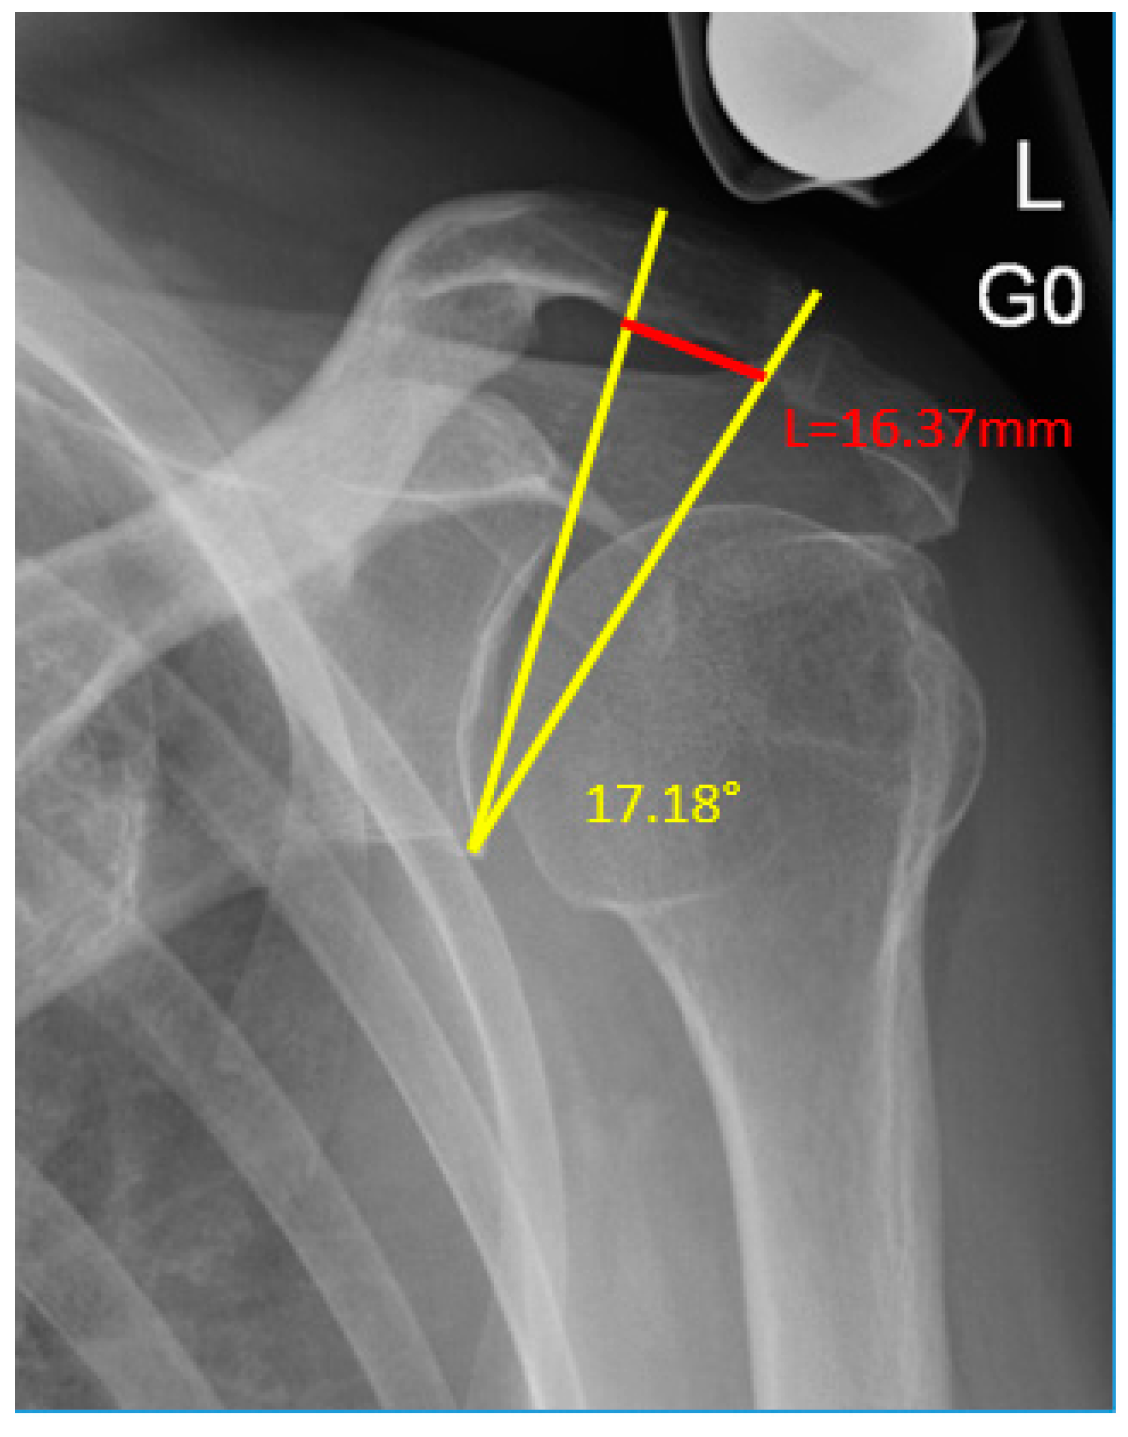

| Short Sclerotic Line [mm] | 16.25 (5.02) | 13.09 (3.98) | 0.008 |